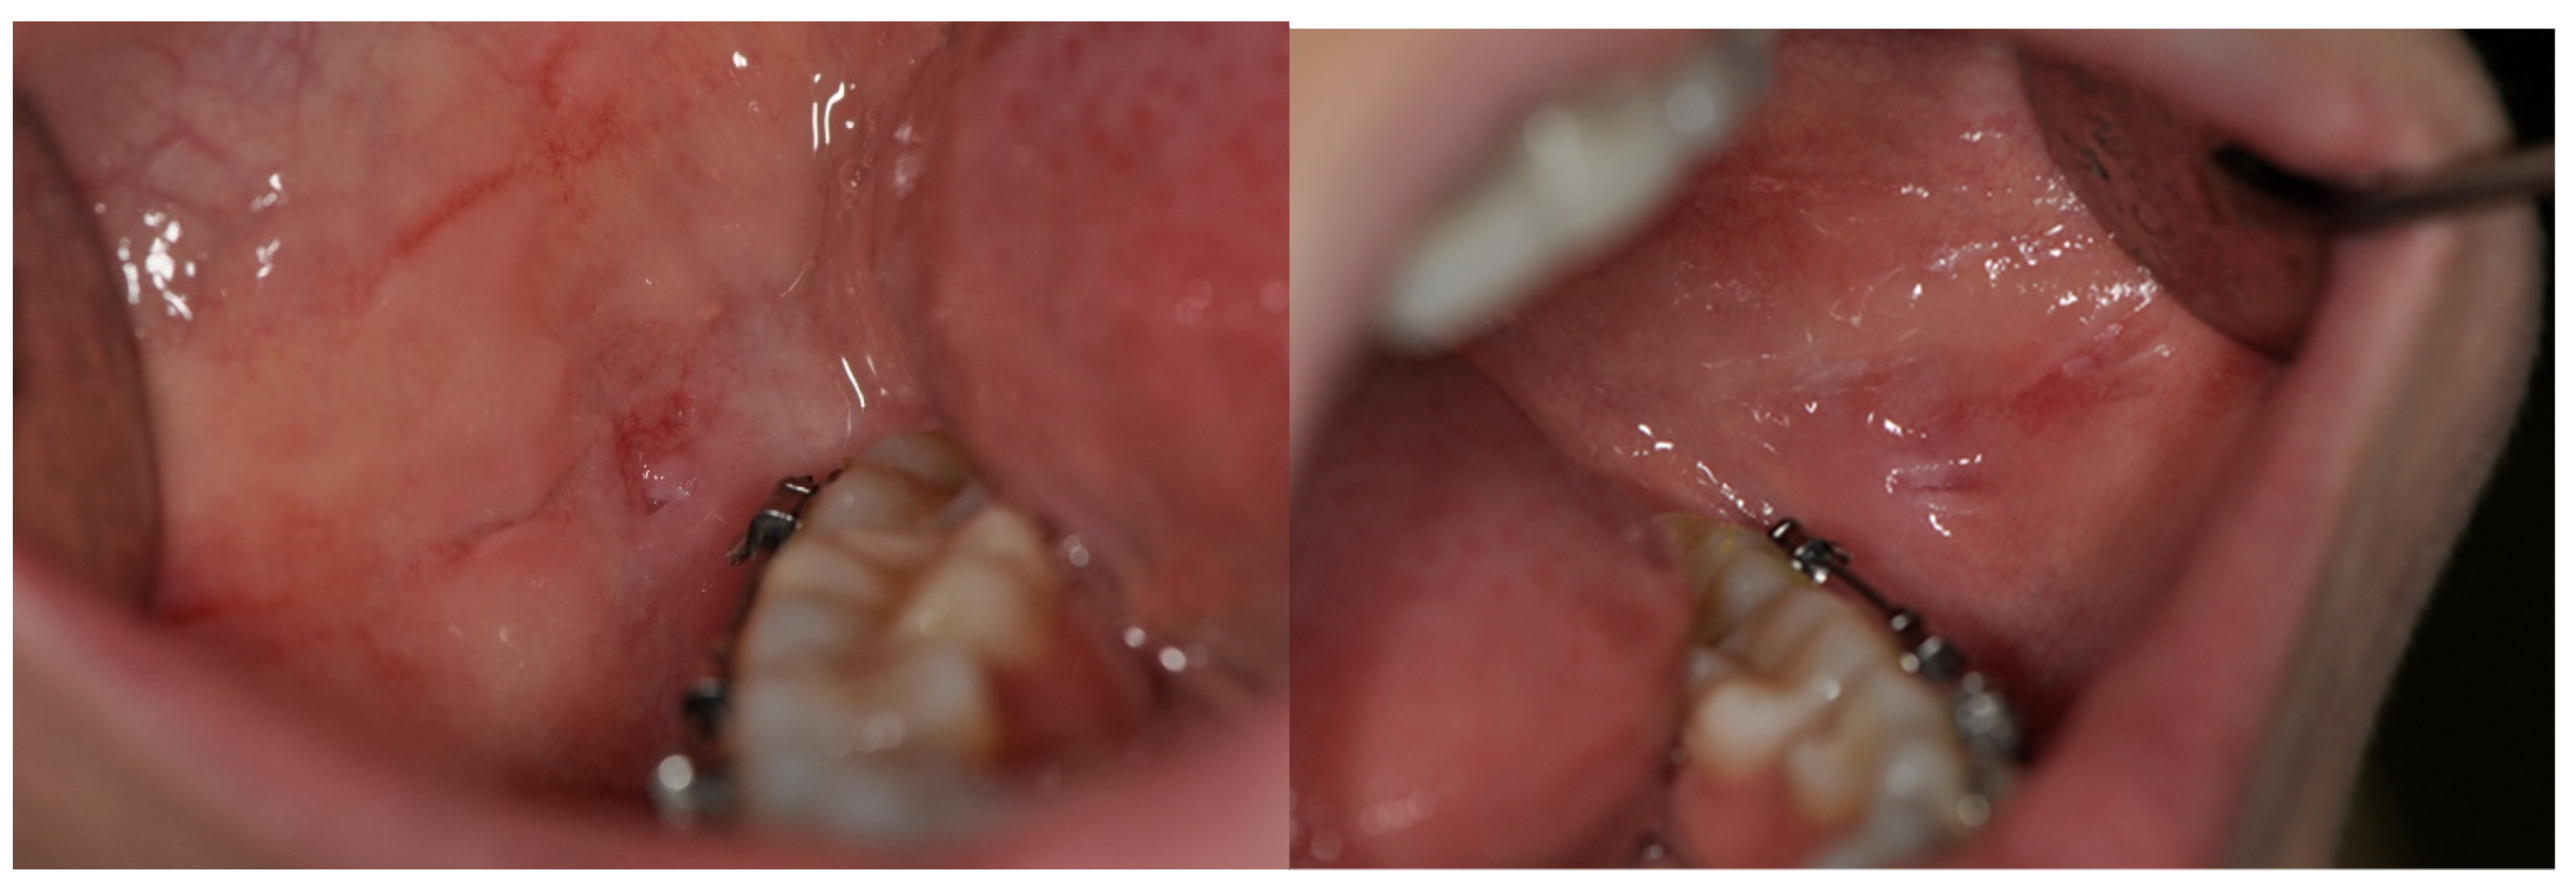

| OLP/OLL (white and white-atrophic forms) | 324 | 11.8 | 62.0 | 268 | 14.6 | 62.5 | 56 | 6.1 | 60.0 |

| OLP/OLL (erosive/bullous forms) | 62 | 2.2 | 66.0 | 47 | 2.6 | 67.0 | 15 | 1.6 | 65.0 |